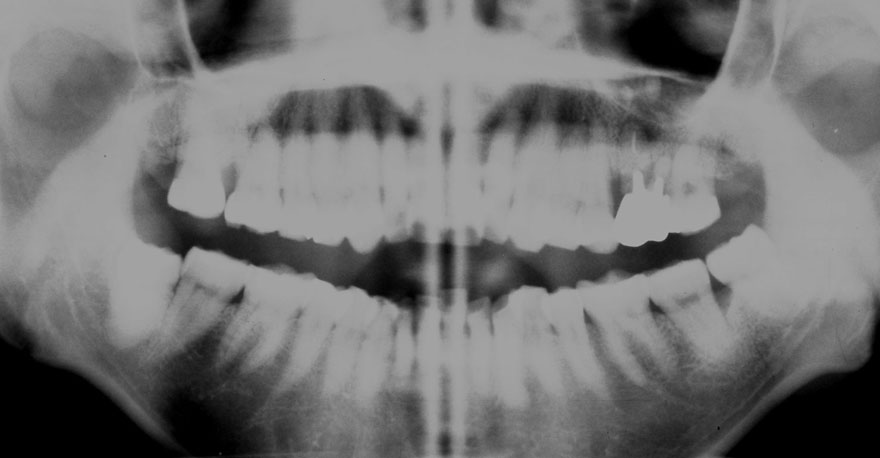

初診時 18歳 女性 平均歯槽骨喪失量:0.87mm

28年後 46歳

平均歯槽骨喪失量:1.40mm

28年間喪失量:-0.52mm

年間喪失速度:-0.02mm

(ケア頻度:5.96ヵ月ごと)